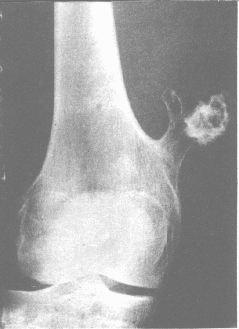

| 股骨单发性骨软骨瘤。股骨下端内侧带蒂状突起,端部呈菜花状,并有浓白钙化。

1.为从长骨干骺端向外突出的类圆形或长圆形骨质形,以蒂状或宽基底与骨相连。由松质骨和皮质骨构成的蒂或基底部各与干骺端相应骨质相连。 2.肿瘤游离侧往往由部分钙化的软骨构成,可呈密度不匀、凹凸不平或菜花状形态。肿瘤中如见到密度减低区,或环状、半环状、斑点状钙化时,则代表软骨组织。 3.小腿或前臂大的骨软骨瘤可压迫邻近的骨骼,使后者产生边缘整齐、光滑的凹陷。 4.多发且大的外生骨疣可引起明显畸形。 |